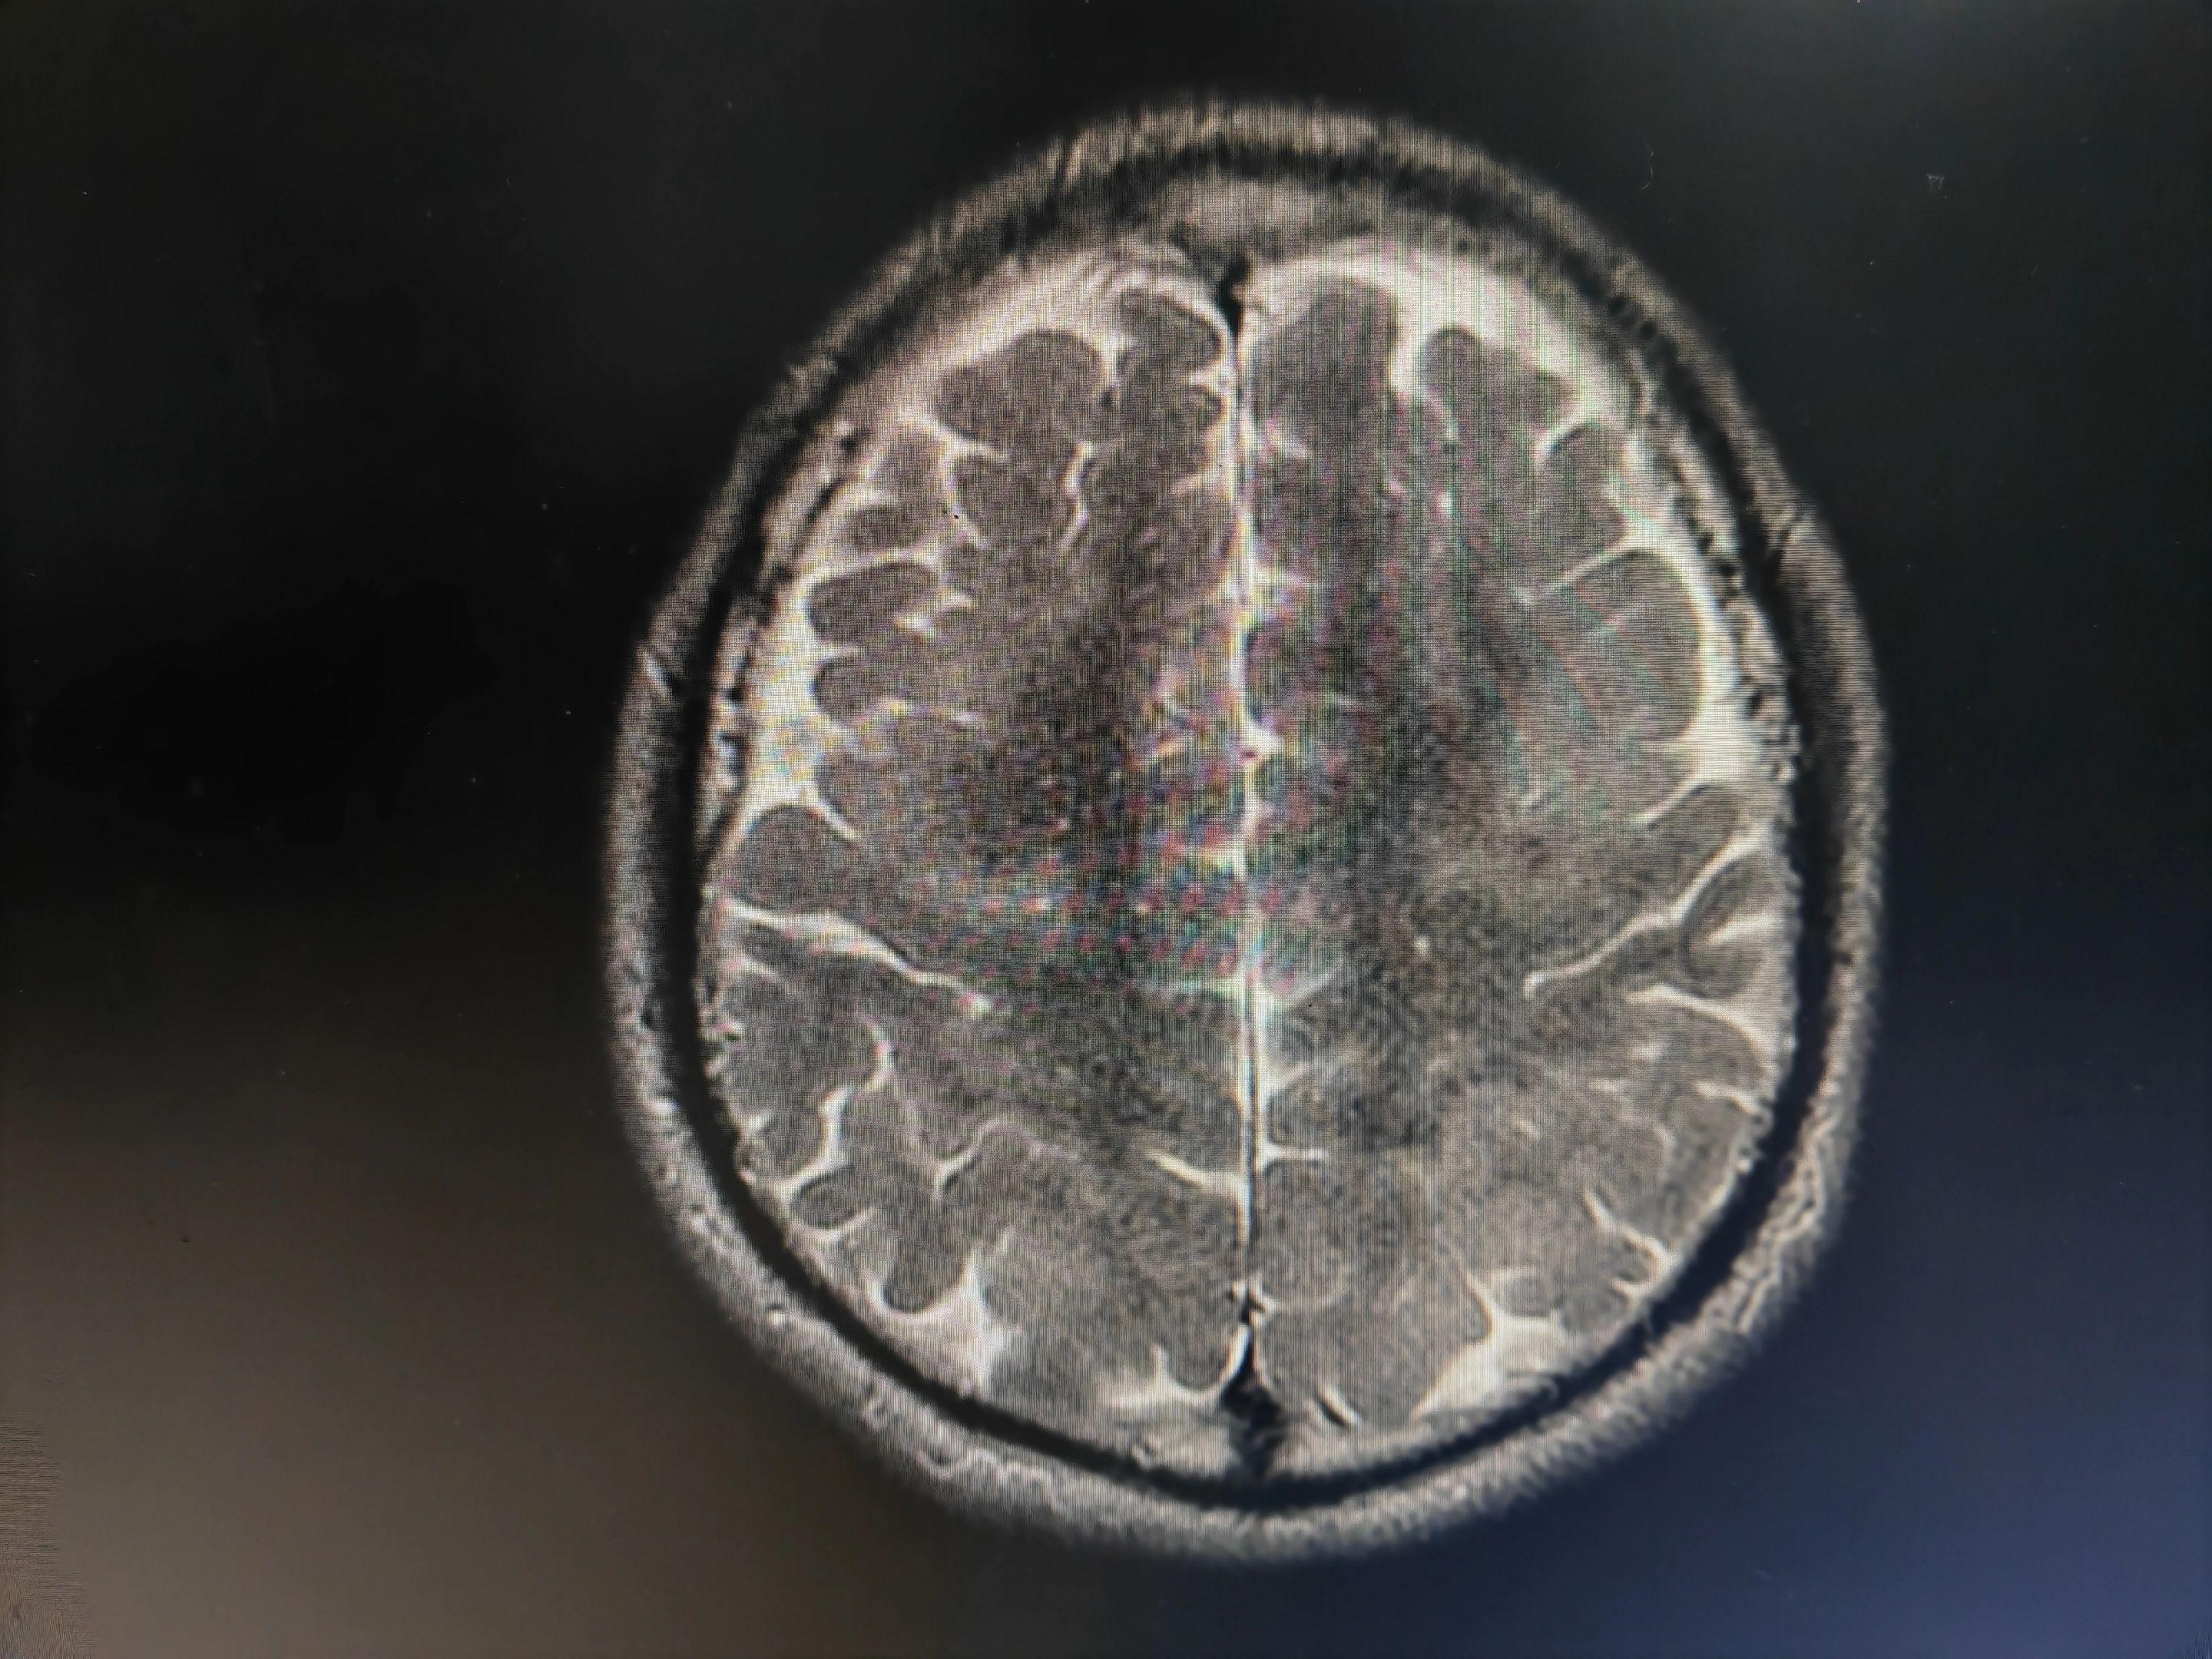

意识模糊伴言语不清的病人 中毒代谢性脑病几种最重要的影像学表现:白色即为受累区域,包括双侧对称性基底节和/或丘脑受累(图A),对称性齿状核受累(图B),皮层灰质受累(图C),对称性脑室周围白质受累(图D),皮质脊髓束受累(图E),胼胝体受累(图F),不对称性白质受累(脱髓鞘疾病;图G),枕顶枕部血管源水肿(图H),脑桥中央受累(I)。